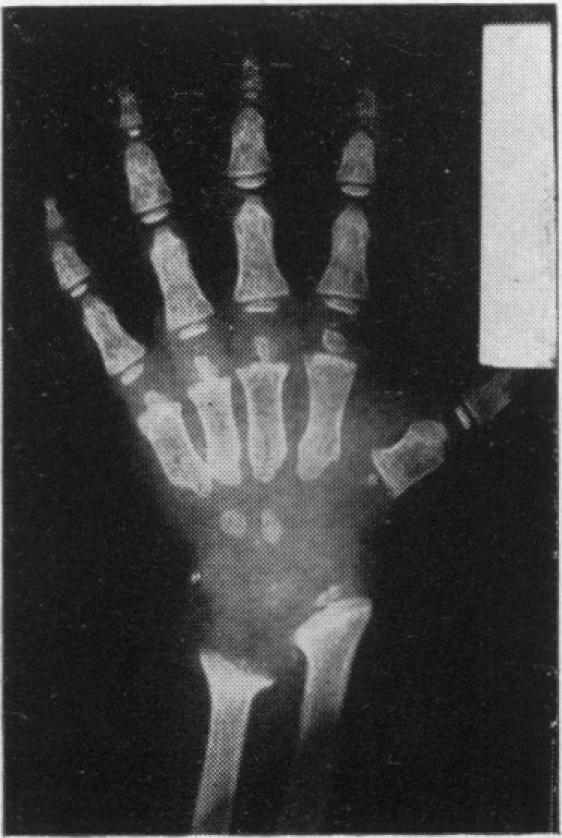

A report of seven cases of chondro-osteo-dystrophy (Morquio's disease).

Arch Dis Child. 1954 Feb;29(143):7-11. doi: 10.1136/adc.29.143.7.